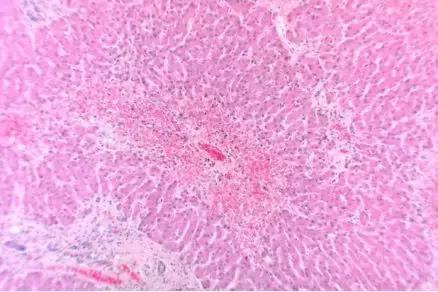

血液中的凝血酶

在显微外科、包括整形和重建手术后有一种棘手的并发症——“静脉淤血 ” 。手术中的血管被切割后可不会意识到自己会被人工缝合好,为了避免人体失血过多,血管内壁会释放凝血物质,导致术后会出现静脉血管血流受阻或淤积的情况。

一旦没有形成有效的静脉回流,手术的器官就会出现淤紫和肿胀继而坏死。如果想真正让血液流通起来,重建血液循环是最关键的步骤。

而水蛭用来治疗这种病症最好不过,它不仅可以持续地吸走手术部分淤积的血液,防止血栓形成,还可以分泌化学物质从而阻止伤口处血液凝块。也就是说,它能使伤口持续流血而不会凝固,直至人体自身的动静脉循环畅通无阻。